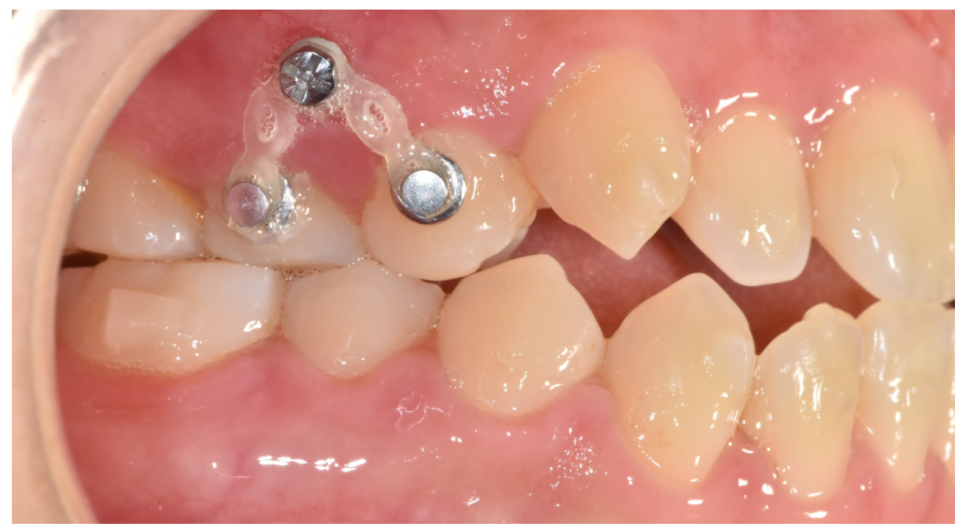

230909

이름 그대로 굉장히 작은 나사입니다.

뼈에 고정하여 치아 뿌리에 힘을 전달하는데요.

치아 이동의 방향을 잡아줍니다.

교정력을 정확하고 효과적으로 전달해주죠.

무엇보다 가장 큰 장점은 교정 기간을 단축시킬 수 있습니다.